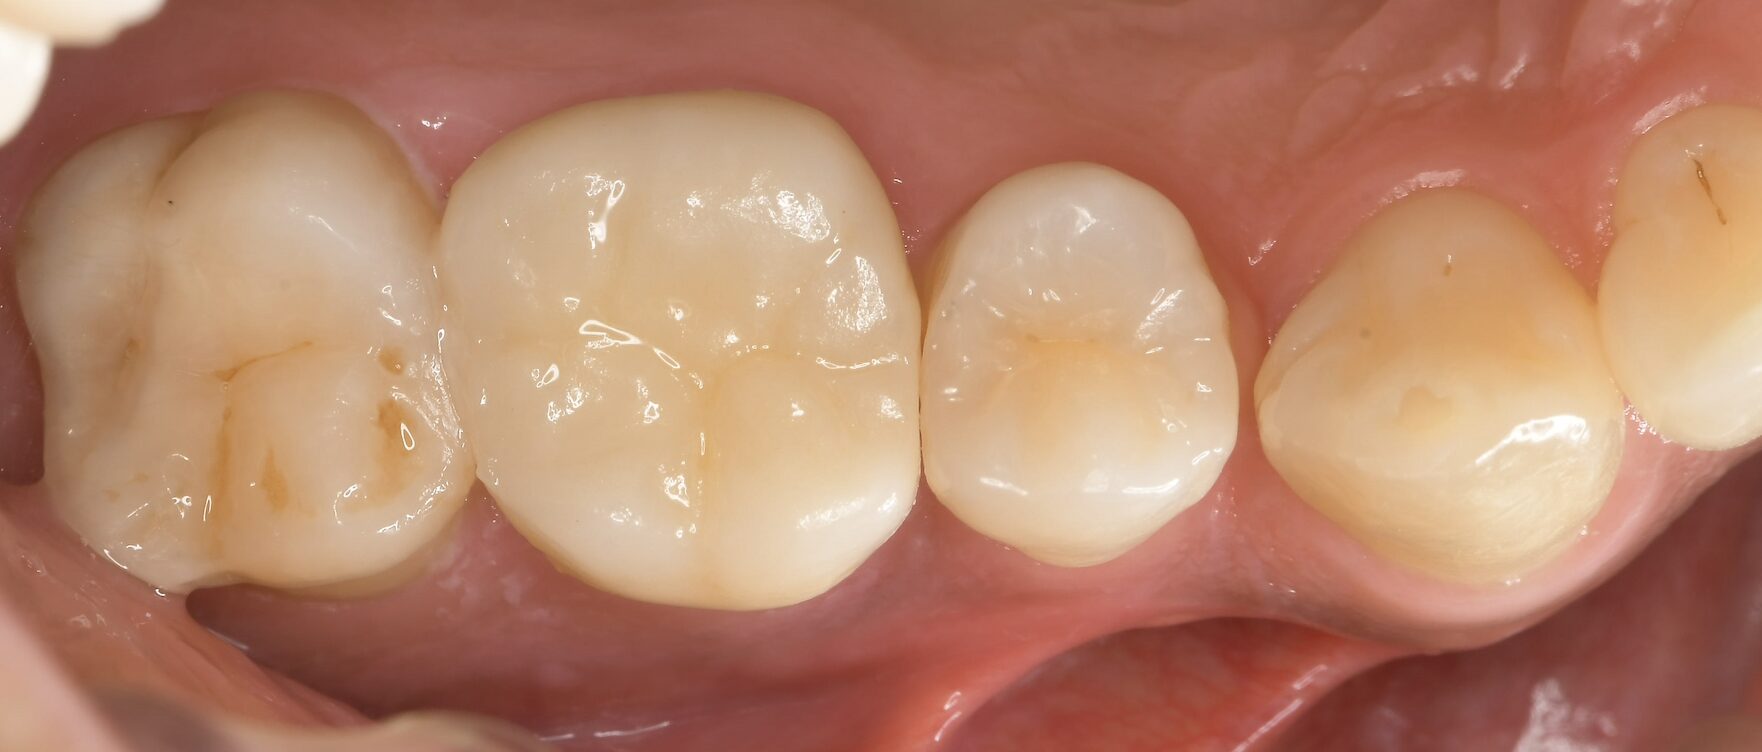

症例 上顎第一大臼歯抜髄処置 2025.10.02 【主訴】 上顎第一大臼歯部の自発痛出現にて、歯内療法専門医受診希望 【背景】 上顎第一大臼歯部に自発痛出現し、根管形態の複雑さから、歯内療法専門医にて治療を示唆 診査診断後、通報に従い、一回の処置で歯内療法及び支台歯築造まで終了し、 仮歯にて1週間ほど経過観察し、セラミック修復に至る 治療前 治療後 セラミック咬合面 セラミック頬側面 【考察】 元々、食いしばり傾向が強く認められる患者であり、メタルインレーにて咬合面をほぼ覆う形態で修復されていた この場合、咬合力コントロールされていない症例では、歯にヒビ(クラック)が生じ、噛むと痛いという訴えや、 神経に達する症状が突然出現するケースも散見される 神経が温存される症例でも、全体的にクラウン形態で修復することが望ましい 【治療回数】 歯内療法 1回 歯冠修復 2回 【治療担当医】 歯内療法 野田哲朗 歯冠修復 白土 州 この記事のタイトルとURLをコピーする